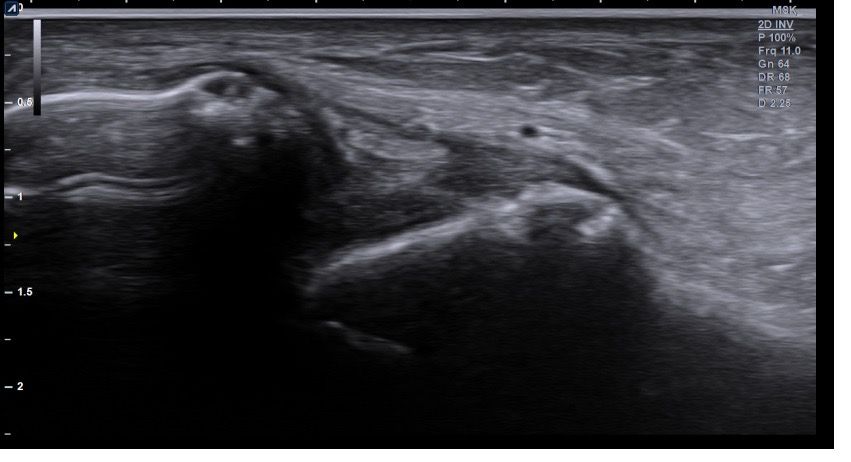

복숭아뼈 미세골절 초음파 사진 관련 질문

발목 접지른 후 치료받는 중인데요 복숭아뼈 미세골절이라고 하셨네요 3월 1일 다친뒤네 3월7일 병원방문후에 위에 초음파랑 엑스레이 촬영했고요 그뒤 반깁스 중입니다. 위에 엑스레이 상에선 안나오는데 초음파 사진에선 미세골절이 맞을까요? 골절이 경미한 수준인지 아니면 중한 건지 궁금합니다 그리고 다음주에 병원 방문 후 초음파 또 촬영하기로 했는데 그때 반깁스도 풀 수 있을까요??

미세골절 같은 경우 엑스레이서 잘 안 보일 수 있고 초음파에서 연부조직과 뼈의 상태를 좀 더 세밀하게 확인하여 확인할 수 있습니다. 미세골절이 경미한 수준이라면 초음파를 통해서 확인이 가능하며 치료 진행 상황에 따라 반깁스를 푸는 시점은 달라질수 있습니다.

발목의 복숭아뼈에 미세골절이 의심되는 경우, 엑스레이에서는 미세골절이 잘 보이지 않을 수 있습니다. 엑스레이는 큰 골절을 잘 확인하지만, 미세한 골절이나 염증 반응은 잘 나타나지 않기 때문이죠. 초음파는 조직의 변화를 보다 민감하게 감지할 수 있기 때문에, 미세골절을 발견하는 데 도움을 줄 수 있습니다. 초음파에서 미세골절이 확인되었다면, 이는 경미한 골절일 가능성이 높아요. 하지만 골절의 정확한 상태나 치유 과정을 판단하려면 정밀 검사가 필요하죠